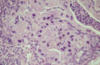

Condition

Aelurostrongylus abstrusus infection